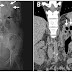

Mujer de 48 años con Fiebre, Escalofrios, Dolor en Flanco Izquierdo, y Oliguria. Pielitis Enfisematosa.

Una mujer de 48 años se presentó al departamento de emergencias por fiebre de 3 días de evolución, asociado a escalofríos, dolor en flanco i...